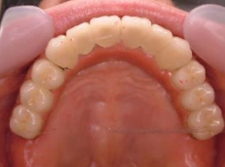

最終補綴物装着

【上顎咬合面観】